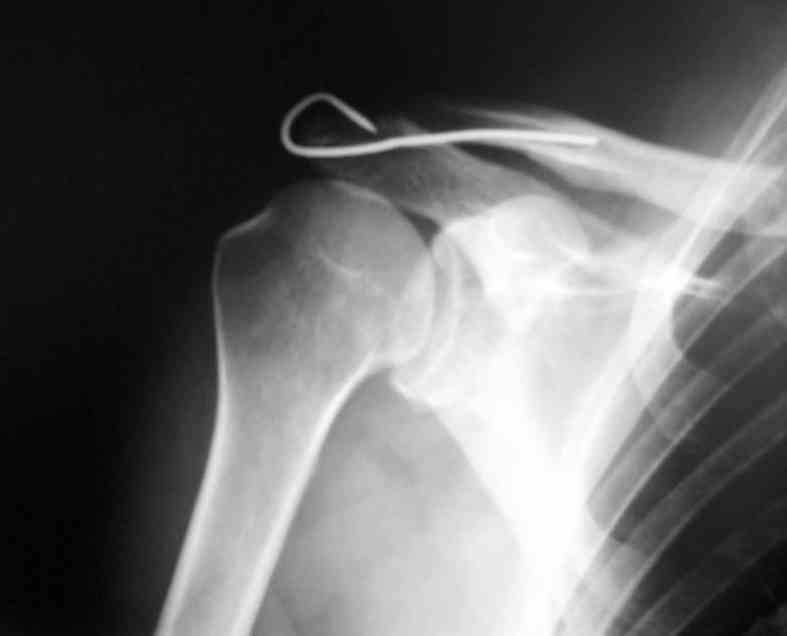

Уважаемые коллеги,высылаю протокол операции (если кому пригодится, буду рад)

Внешний вид больного (травма: 09.10.2007, операция: 11.10.2007) Ориентиры доступа: овальный – пальпируемый акромиальный конец ключицы, линейный – операционный разрез

Введение крючка в подготовленный канал Дистальная часть крючка подведена под акромион и фиксирована на нем путем загибания (вывих ключицы устранен)

Зачем изобретать велосипед. Есть hook plate.

Используем крючковидную пластину (не важно "Синтез", ДЕОСТ или Рыбинскую). Хорошие результаты. Иммобилизация косынкой на 2-3 недели. Когда на нашем рынке еще не было этих пластин - оперировали по Ли-Гольдману (заведующий из Прокопьевска). Как альтернатива - фиксация по Веберу. Но часто видел осложнения - спицы не выдерживают, ломаются. так что в отделении эту методику не применяем.

Уважаемые коллеги, замечательная тема - вывихи акромиального конца ключицы! А замечательна она тем, что нет одного универсального способа лечения. Значит, есть возможность приложить разум. И применять разные методики. Возражаю я только против одной - фиксации спицами в разных вариантах. Уж больно много приходилось видеть случаев миграции сломанных спиц. Но самый необычный случай показал как-то профессор Евгений Костив из Владивостока. В его отсутствие ординаторы фиксировали вывих спицами с петлёй. Через 2 месяца пациент пришёл на контрольный осмотр. Евгений и предлагает ему - уберём спицы, вытащим проволоку от греха подальше. А пациент и отвечает - не до вас мне теперь, кашлял, кашлял я месяц и нашли врачи у меня патологические грануляции в трахее. Взяли на гистологию, готовят к экстирпации гортани с резекцией трахеи. Рак у меня , не жилец я. Что уж там эти спицы!. Но Евгений Петрович настоял - и снимок всё же сделали. А там только одна спица из двух! А вторая - в мышцах здорового надплечья! Сломалась и мигрировала через трахею! Так когда больному об этом осложнении сказали - он руки докторам целовал! От счастья, что это не рак. Снимки зти я сам видел. И спицы в АКС не ставлю. И никому не советую. Начинал же я оперировать эти повреждения по окончанию института - в 1985 году в Кемерово Прокопьевской травматологической области. И начинал, естественно, с Ли - Гольдмана. Все описанные на этом форуме плюсы налицо. За исключением одного минуса - никогда и нигде я более не видел и не делал такого количества резекций АКС по поводу ДОА. Статистически не смотрели, но каждую неделю в ортопедии делали эти резекции. Ведь по этой методике, если мне память не изменяет, АКС пенетрируется не самым тонким стержнем. Или я ошибаюсь. По моему нет - отсюда и проблемы. Далее был этап какого-то лавсана с частым его извлечением. Затем - чрезключично-клювовидная фиксация винтом (винтами)из мини-доступа под контролем ЭОПа. Но иммобилизация здесь обязательна - минимум 3 недели. И эту операцию я делаю. Тем более, что появление hook plate не решило проблем. И не только в цене дело. Кстати, синтезовская hook plate даже в блокированной версии минимум в 2 раза дешевле, чем отражено на форуме. Да ладно, не о деньгах пациентов вопрос в принципе. С нашей точки зрения - чем крупнее, массивнее и активнее пациент - тем лучше себя ведёт этот имплантат. Наилучший функциональный результат я получил у молодого защитника сборной страны по хоккею. Через 2 месяца он уже играл. А пластину убрали только по окончанию сезона. Но вот субтильному юноше или очаровательной девушке я эту пластину ставить не буду. Слишком агрессивно для них. Обойдусь винтом. С уважением, Волна